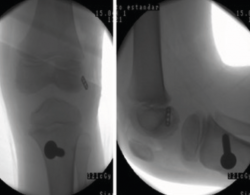

Figura 5. Radiografía de control intraoperatoria de un paciente de 6 años con reconstrucción según la técnica transepifisaria de Anderson.